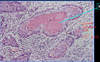

Pathologic characteristics of squamous cell carcinoma

- central

- often cavitate

- keratinization

- intracellular bridges